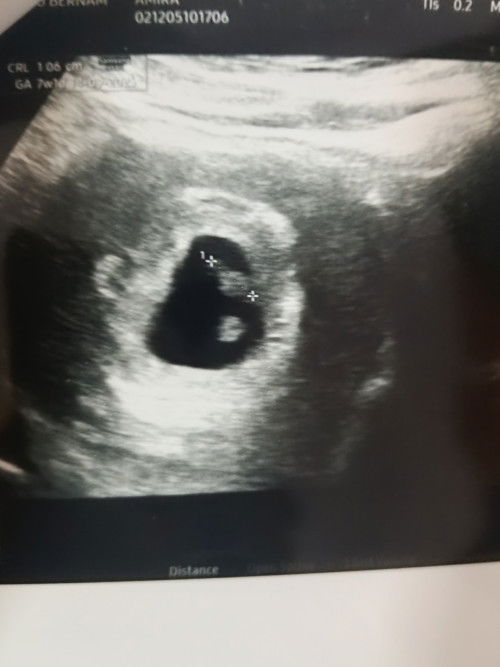

Saja nak share , Semalam start pagi muntah air.. lepastu tengah hari muntah, then petang muntah.. ingat malam dah tak muntah dah.. nak dibuatkan cerita pergi la kedai makan sebab perut lapar .. then borak2 spendtime kebetulan ada kawan datang kedai .. masa tu okay lagi.. bila nak balik menuju kereta.. tiba tiba boom muntah mengejut ( muntah tepi pokok ) .. muntah everything makan tadi..Memang sangat terseksa ya waktu muntah bila kat luar.. Then suami belikan la susu coklat goodday untuk tambah tenaga sebelum balik rumah.. tak lama kemudian dalam 10 minit muntah susu tu semula dalam kereta ..nasib dalam kereta dah standby plastik … sakit sangat rasa down sangat.. Memang fasa fasa mencabar ke waktu 9-10 week ni?😭😭😭 Mommy2 kat luar sana yang dah ada pengalaman.. korang rasa gender apa yang mual teruk di fasa 1TM ni?🤣#Needadvice #firstmom #sharing